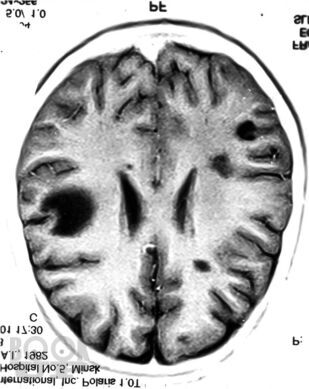

В руководстве обобщен практический опыт и анализ современной литературы по диагностике и лечению 30 редких или атипично протекающих неврологических синдромов и болезней. Обсуждаются аспекты этиопатогенеза, клинической картины, дифференциальной диагностики, наиболее типичные тактические и терапевтические ошибки.